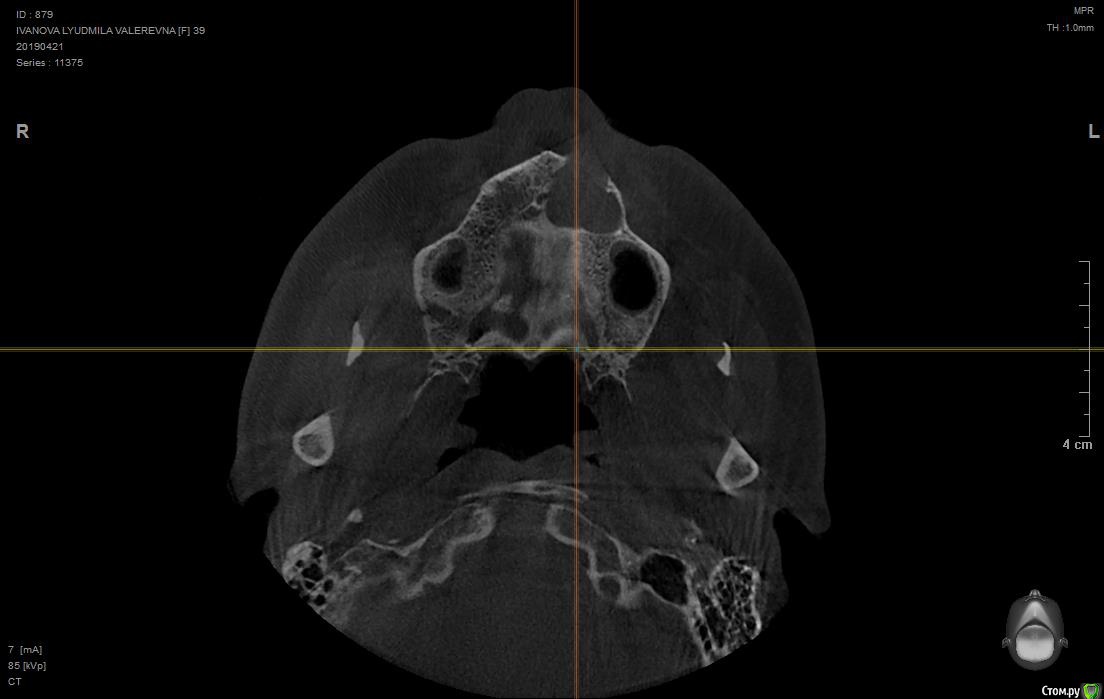

людмила10 Опубликовано 28 апреля, 2019 Поделиться Опубликовано 28 апреля, 2019 Здравствуйте доктора , помогите разобраться была у стоматолога сделали кт оказалась огромная киста на двойке уже добралась до верхней челюсти и повредила мою кость, когда то на этом зубе возникла большая киста мне сделали резекцию корня что бы спасти зуб потом через пару лет оказалось что там рецидив, правда киста была маленькая, и не болела потом появился свищ, от туда выходил гной и кровь, сейчас мой врач сказал обратится к челюстно-лицевому хирургу, что бы они сделали мне биопсию так как киста большая и операцию и все от туда убрали потом нарастили мне кость в том месте где ее нет и потом он через пару месяцев поставит мне имплант , ночь не сплю всего боюсь есть не могу аппетита нет , были ли у вас такие пациент доктора, возможно все это сделать и не сойти с ума ..https://му-fils.ru/2j8jim кодовое слово QGAYKZDHSU Ссылка на комментарий

___49___ Опубликовано 28 апреля, 2019 Поделиться Опубликовано 28 апреля, 2019 Не смог скачать КТ , срезов маловато для более объективной оценки , из того что вижу - зуб уже лучше удалять вместе с кистой , проверка соседних зубов на витальность ( живые или нет) , биопсия желательна . Ссылка на комментарий